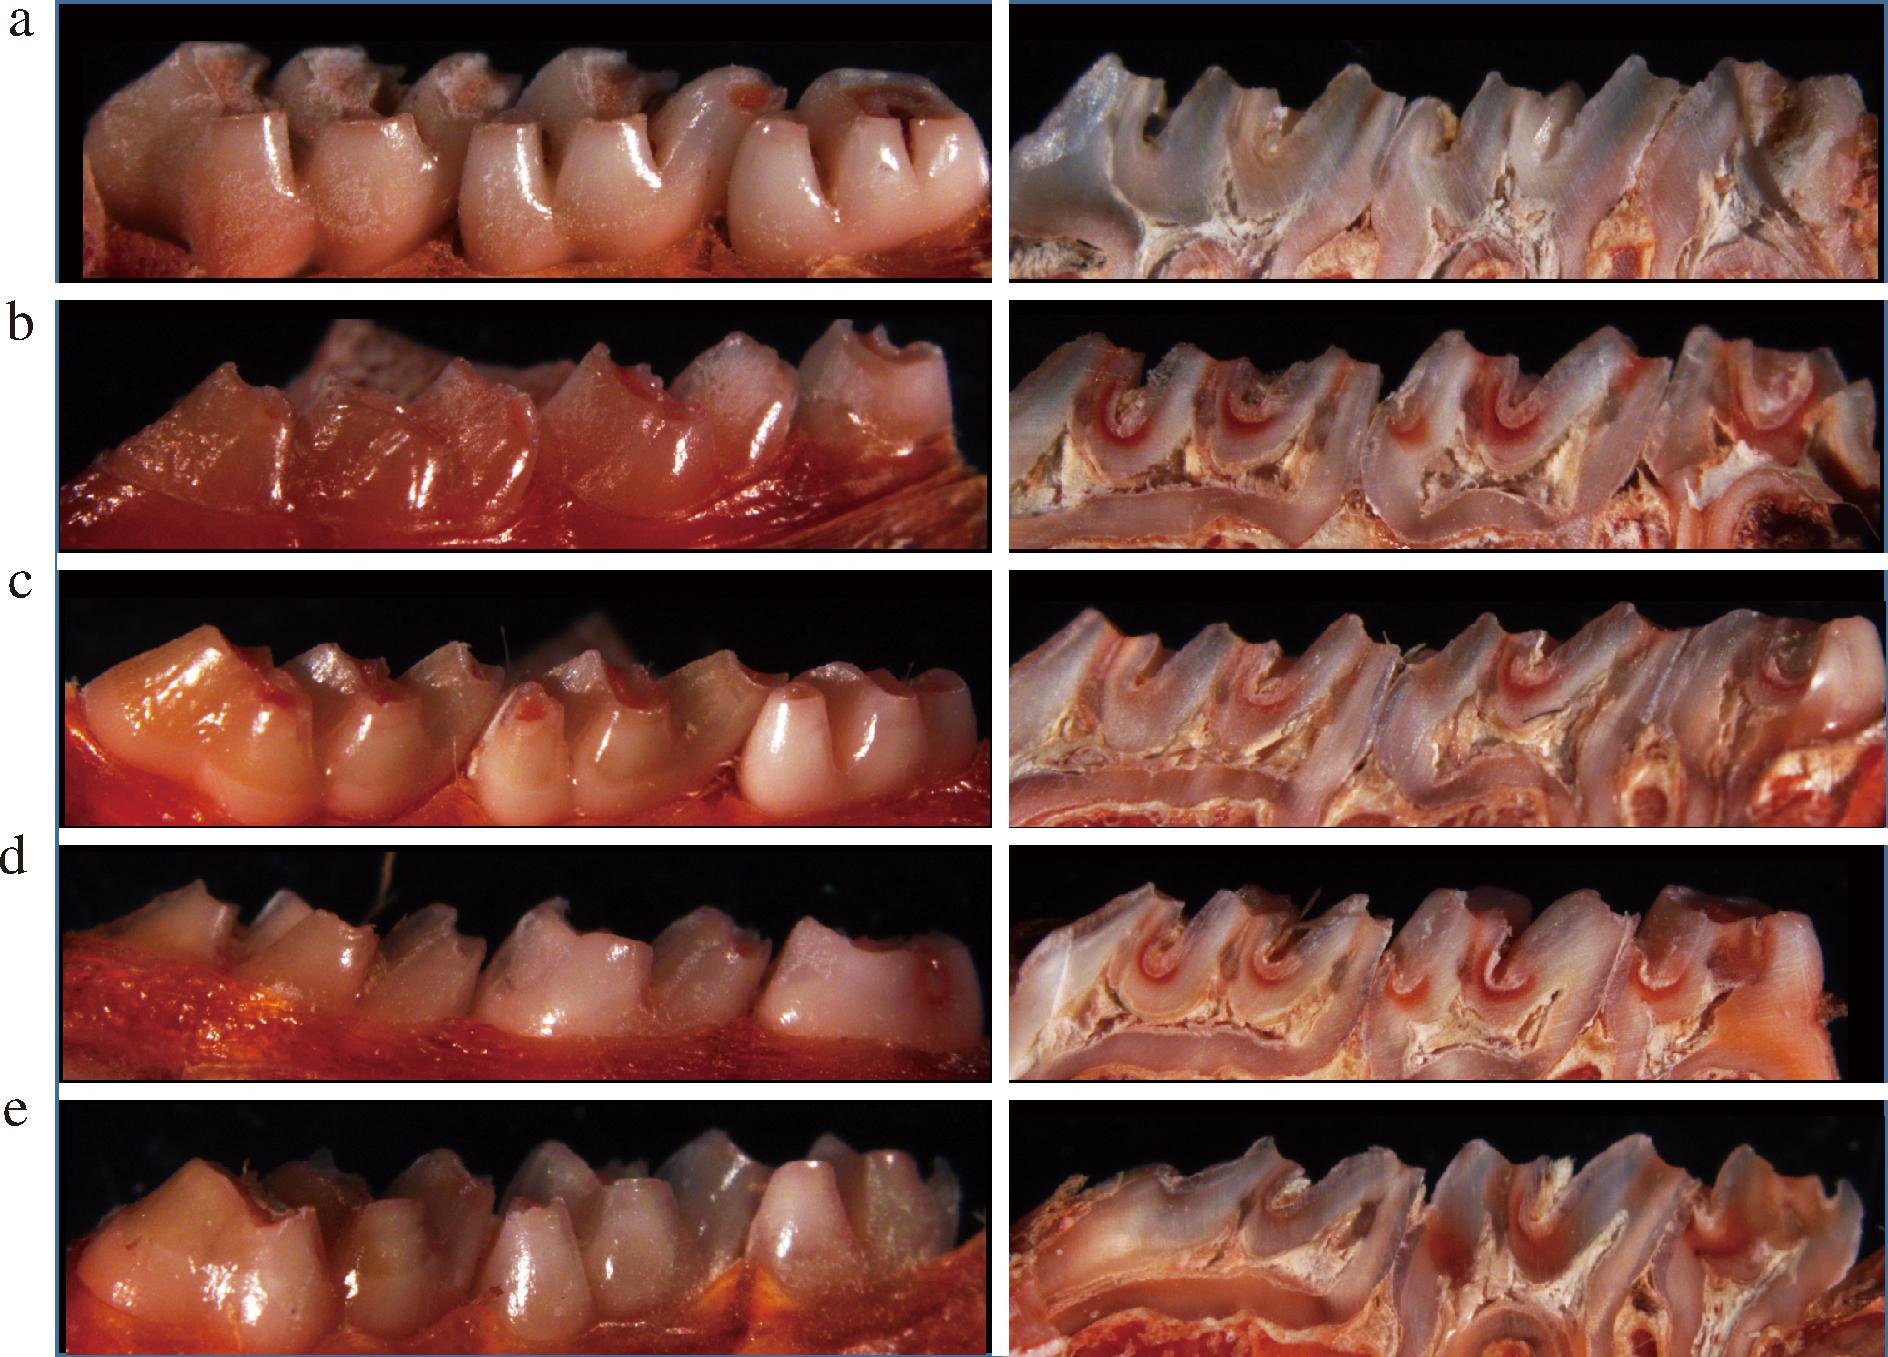

龋损的牙体硬组织会由于脱矿而使微小孔隙增多,可以被紫脲酸铵染色剂染成红色[32]。用体视显微镜观察染色后的大鼠牙齿,结果见图5。空白组磨牙光滑面、纵切面的窝沟及邻面均没有被染上颜色,说明空白组无龋损(图5-a)。而模型组光滑面被染成红色且面积较大,纵切面显示所有磨牙的窝沟均被染成红色,部分邻面也被染色(图5-b)。经过洗必泰和复合益生菌干预后,大鼠磨牙的光滑面、邻面及窝沟染色程度都有所下降,但是辅料组邻面及窝沟面染色程度变化不明显。

a-空白组;b-模型组;c-洗必泰组;d-辅料组;e-复合益生菌组

图5 染色后大鼠磨牙及其纵切面

Fig.5 Stained rat molars and their cross-sections